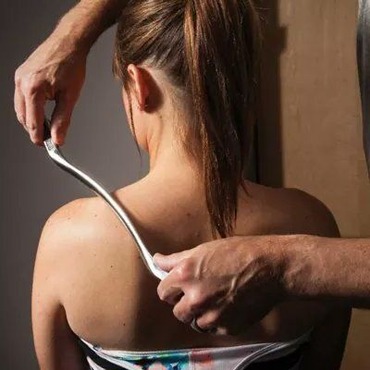

Bel Ağrısı

Bel ağrısı, genellikle uzun süreli oturuş, yanlış postür, ağır kaldırma veya belirli bir aktivitenin tekrarı sonucunda ortaya çıkabilir. Bel ağrısı, alt sırt bölgesinde hissedilen rahatsızlık, sızı veya şiddetli ağrı şeklinde kendini gösterebilir. Fiziksel aktivite eksikliği, kas zayıflığı, disk herniasyonu veya bel fıtığı gibi faktörler bel ağrısına katkıda bulunabilir. Bel ağrısının tedavisinde manuel terapi, egzersiz programları, postür düzenlemeleri ve belirli durumlarda ilaç kullanımı gibi yöntemler kullanılır. Bel ağrısı sorunuyla başa çıkmak için bireysel bir tedavi planı oluşturmak, ağrıyı hafifletmek, hareketliliği artırmak ve uzun vadeli rahatlama sağlamak amacıyla önemlidir. Tedavi, bel ağrısının nedenine, şiddetine ve bireyin özel durumuna göre uyarlanmalıdır.